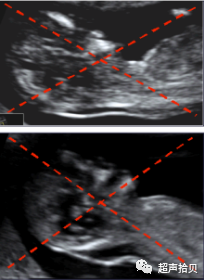

• 约5%的病例中,胎儿颈部会被脐带环绕。研究已发现,NT的测量值会因此而增加

• 在这样的病例中,在脐带上方或下方测量NT结果会有所不同。计算风险的时候,取上方和下方的平均值比较合适。